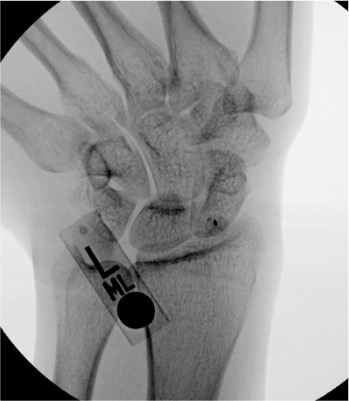

Wrist

Dorsal radiocarpal

Scapholunate interval or radioscaphoid joint; 3–4 cm distal to Lister's tubercle

3–4 mL

Wrist injected volume is small. The radiocarpal compartment holds only 3–4 mL — resistance is felt quickly. Stop injecting if resistance increases before target volume; overdistension causes capsular rupture and contrast extravasation that can obscure compartment communication findings.

Finding

Fluoroscopic Appearance

TFCC tear

Contrast from radiocarpal joint fills the distal radioulnar joint (DRUJ)

Scapholunate ligament tear

Contrast from radiocarpal joint fills the midcarpal compartment through the scapholunate interval

Lunotriquetral ligament tear

Contrast fills midcarpal from radiocarpal through lunotriquetral interval

Wrist: wrong compartment

Wrist has three compartments (radiocarpal, midcarpal, DRUJ) — each must be entered separately for complete three-compartment arthrogram if indicated; inadvertent midcarpal entry misses radiocarpal pathology